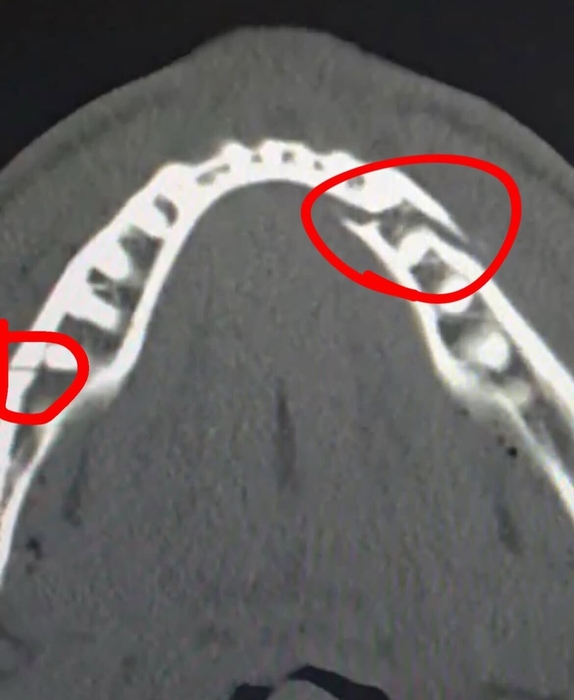

폴은 경기 후 사회관계망서비스(SNS)에 올린 글을 통해 “턱뼈가 부러졌지만, 심장과 배짱은 멀쩡하다”며 양쪽이 모두 골절된 턱뼈 엑스선(X-ray) 사진을 공개했다. 두 군데가 부러져 턱뼈가 3조각이 난 상태였다.